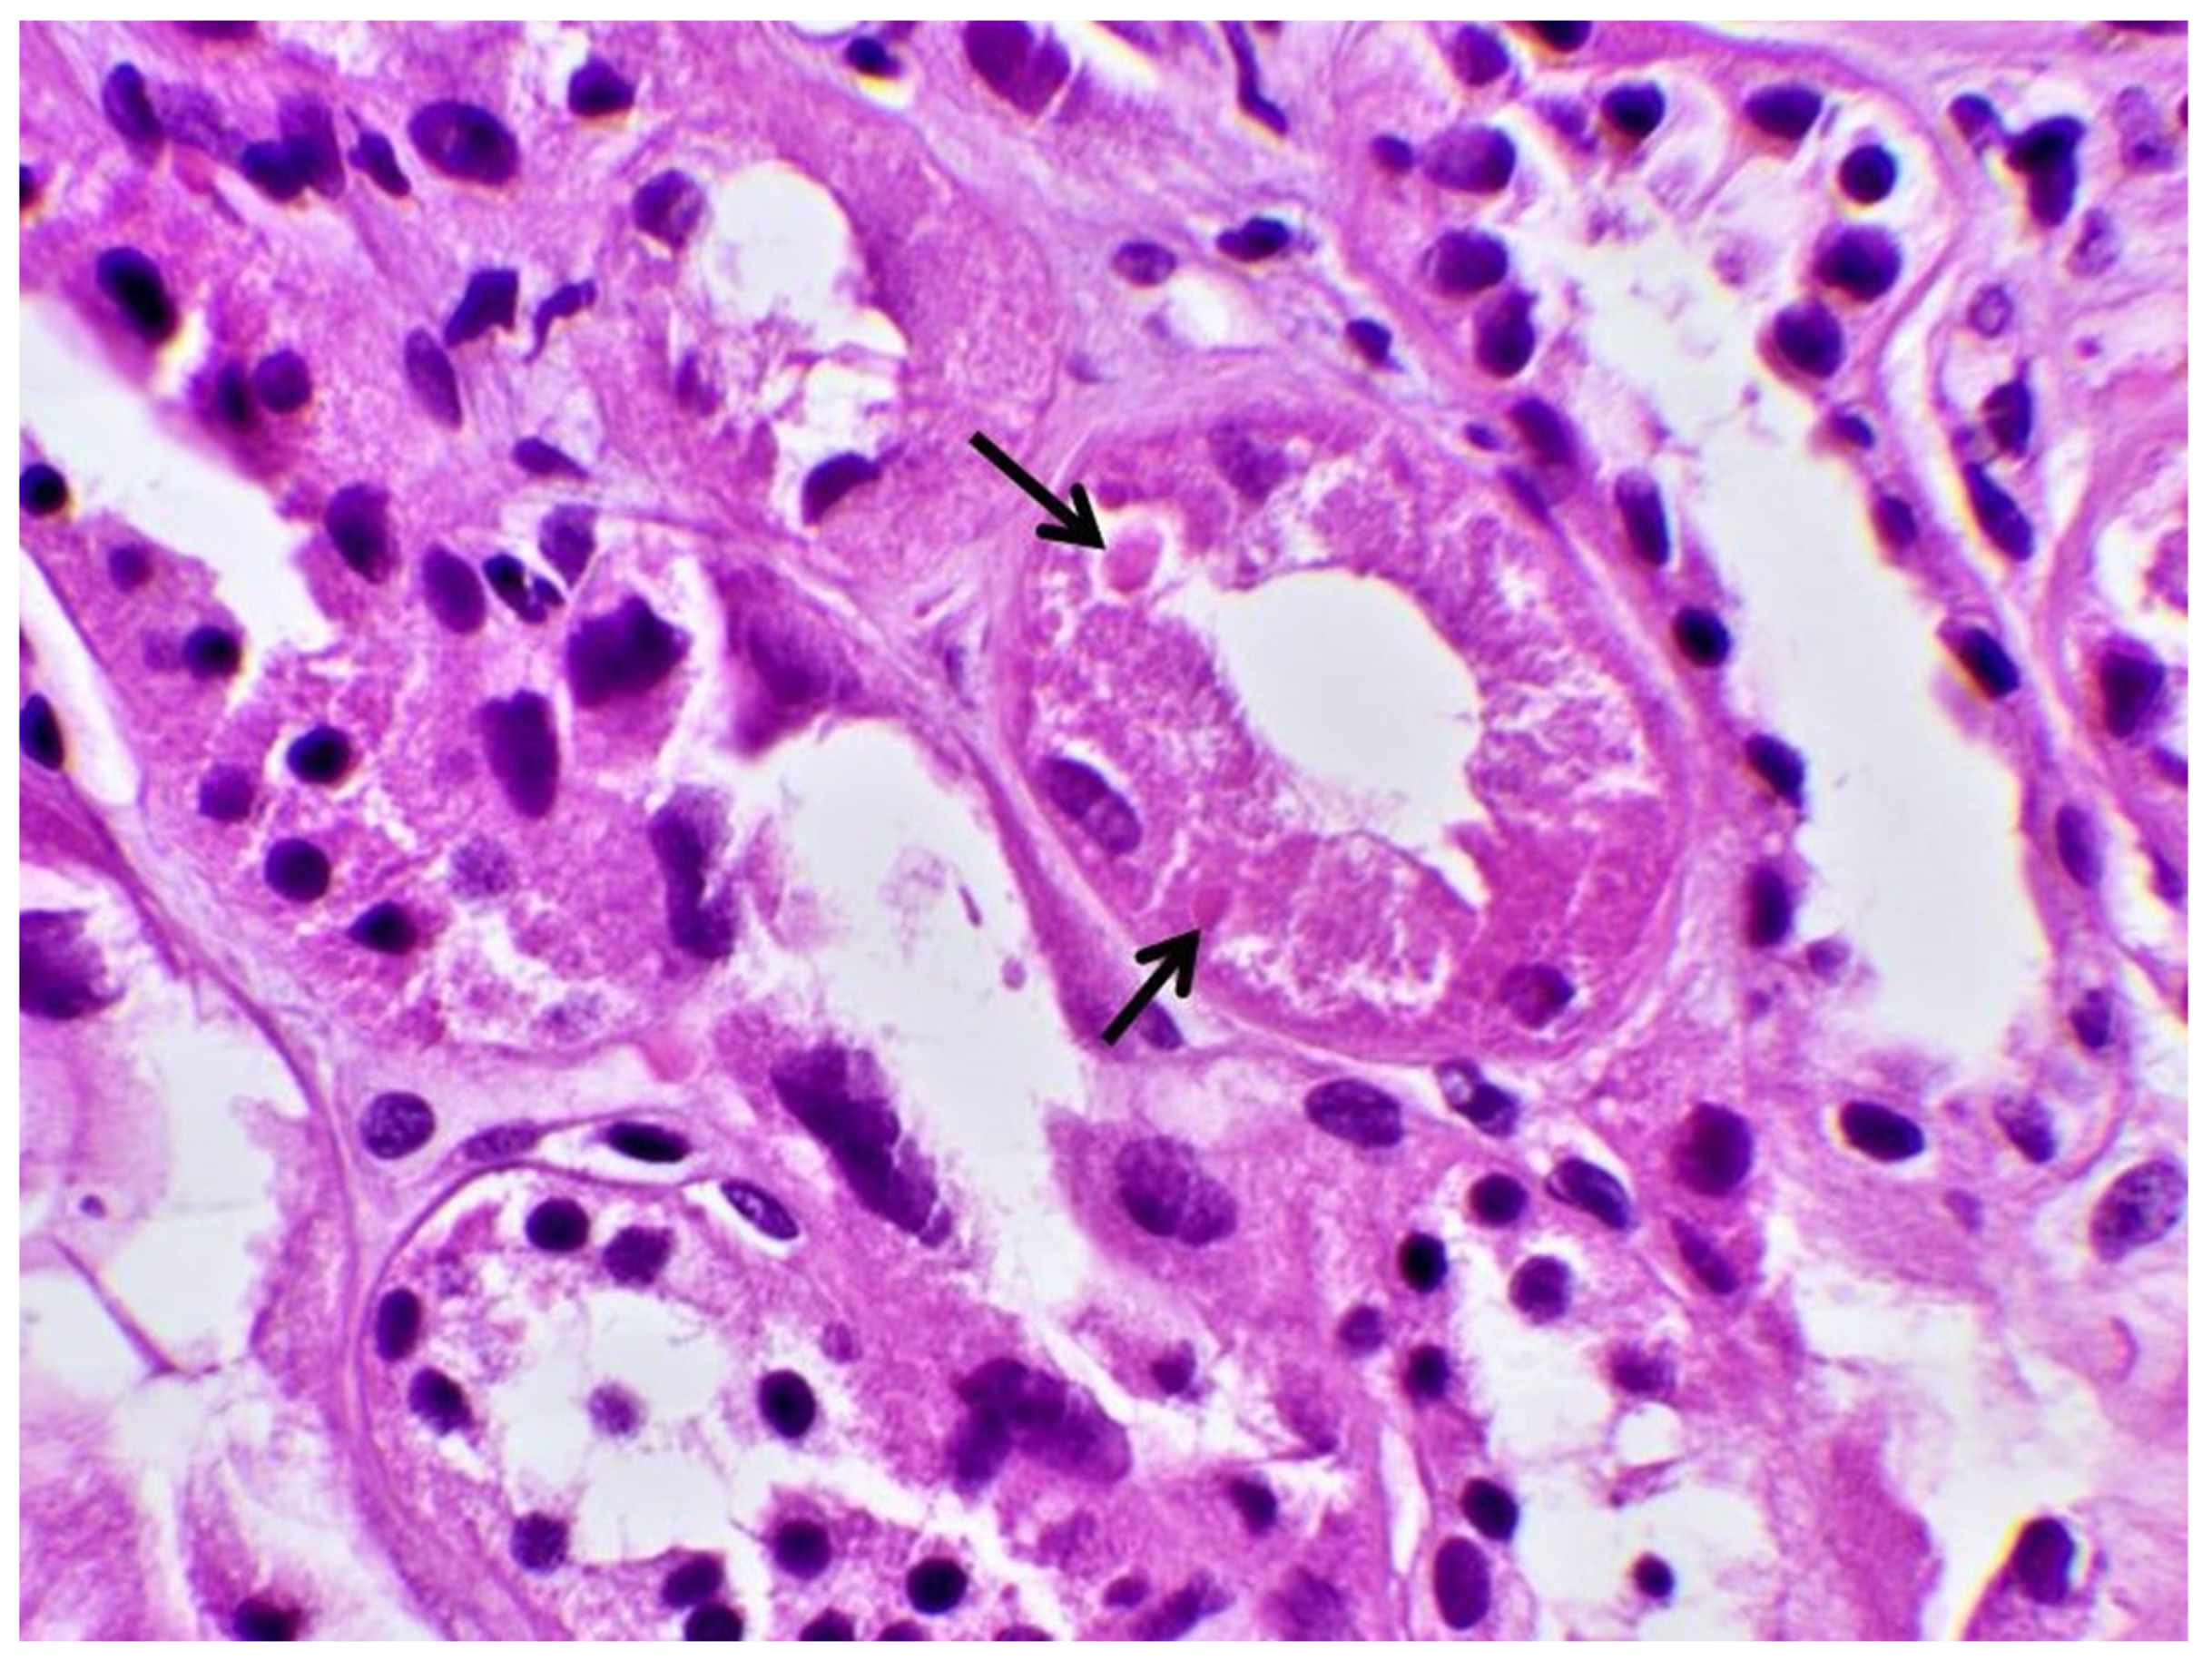

| Biopsy | Proximal Tubular Injury | Not performed | Not performed | Not performed | Proximal Tubular Injury |